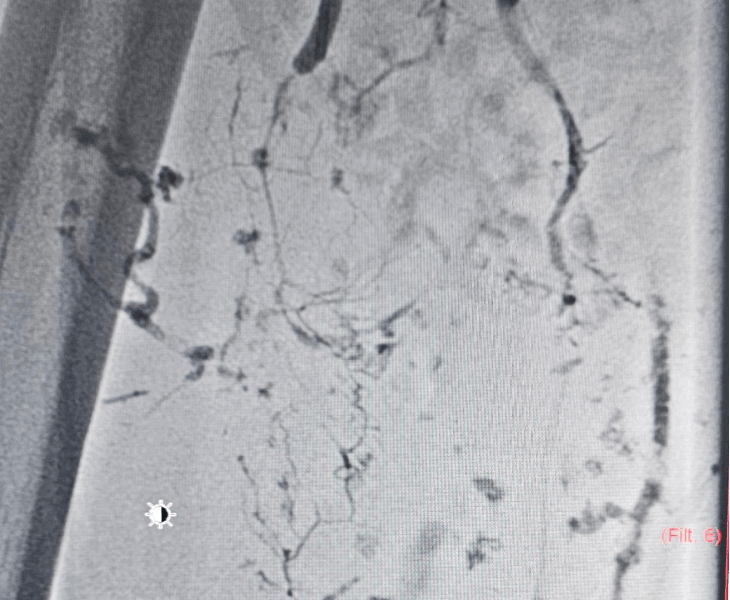

Post treatment

Large lesions may need more than one session. We monitor clinical response and repeat imaging to confirm sustained reduction.